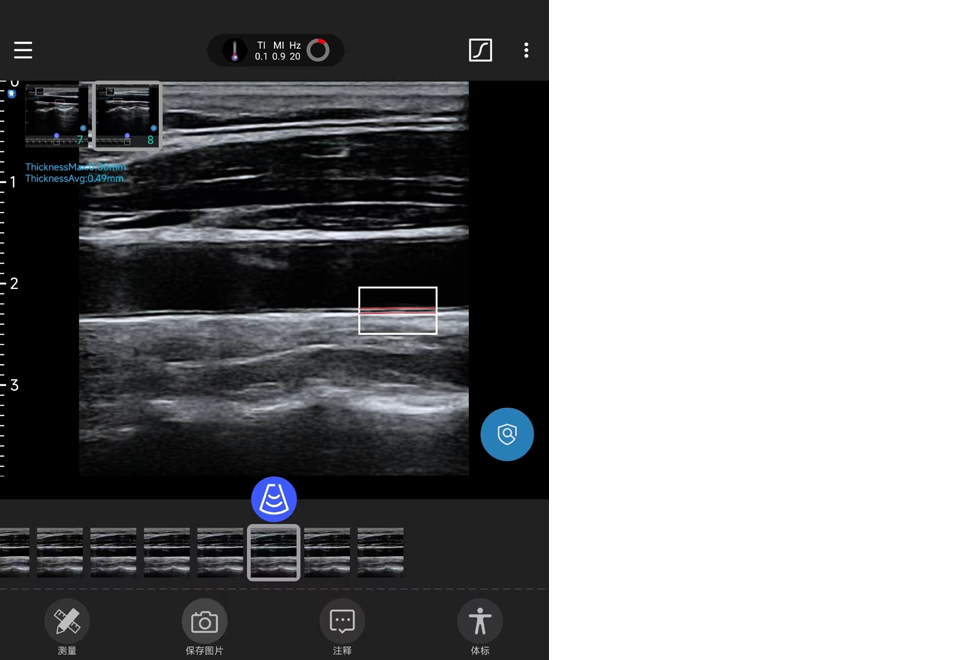

心血管壁垒技术-IMT实时识别与量化AI技术

技术特点

IMT实时识别与量化AI技术,对连续扫查过程中的实时IMT都将纳入AI识别的范畴,从而不漏筛可能的内膜增厚位置。准确性高:相比传统只进行单帧的IMT测量评估,本技术将对Cloop中全部的IMT进行自动测量,并得出最大的厚度位置,从而摒弃传统测量值偏低的因素。评估准确:本技术依据病患性别、年龄、左右叶信息充分评估当前指标的增厚可能性,缓解了对超声医师的经验依赖。